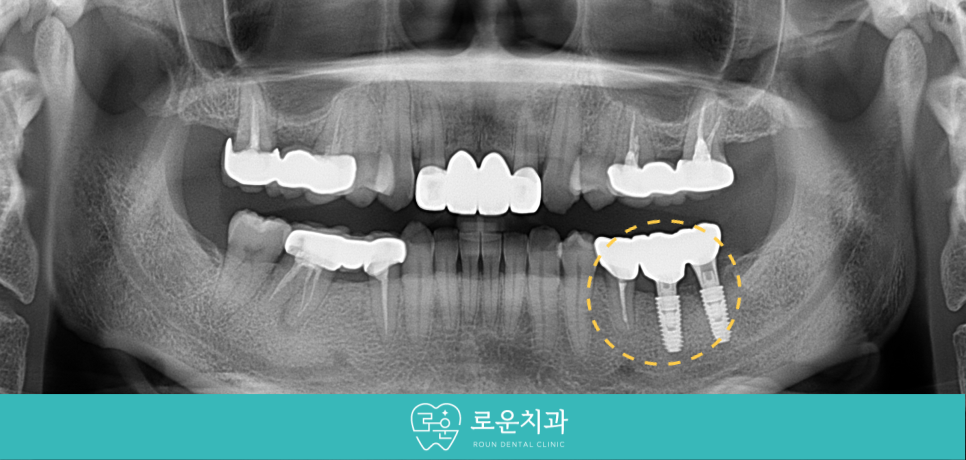

용호동임플란트 로운치과에서는

가급적 자연치아를 살릴 수 있는 방향으로

꼼꼼하게 검사를 진행한 결과

아래턱 왼쪽 두 번째 작은 어금니(#35)는

보철물 제거 후 재 신경치료를 통해

단독으로 크라운 수복을 도와드리기로 하였으며,

두 번째 큰 어금니(#37)는

발치 후 바로 앞의 상실 부위와 함께

용호동임플란트 식립을 도와드리기로

치료 계획을 수립하였습니다.

염증이 심했던 부위이기 때문에

잇몸뼈가 차오르고 아물 때까지

충분히 기다린 뒤 용호동임플란트 식립을

도와드리기로 하였습니다.

그동안 상실된 부위의 용호동임플란트를

먼저 식립을 도와드렸는데요.